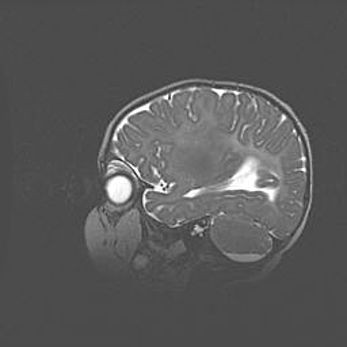

Подострая гематома правой гемисферы мозжечка.

Наружная гидроцефалия.

Возраст: 15 дней

Вес: 3100 г

Пол: женский

Окружность головы: 37 см

Срок гестации: 35-36 недель

При открытой наружной форме гидроцефалии у новорожденных расширяются и переполняются субарахноидные пространства.

Кровоизлияния в мозжечок имеют две клинико-анатомические формы: полушарные гематомы и кровоизлияния в червь.

К появлению этой патологии может привести: повреждения головного мозга, возникающие в результате асфиксии и гипоксии плода при беременности, или травмы во время родов. Редко гематома мозжечка может быть результатом первичной коагулопатии и сосудистой мальформации, диссеминированном внутрисосудистом свертывании, изоиммунной тромбоцитопении.